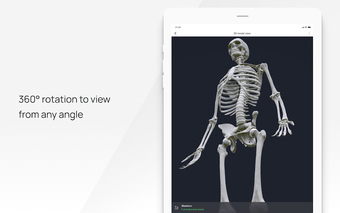

In this atlas of human pathologies you can learn about diseases, their causes, symptoms, and treatment. It contains all the essential information about the anatomy of the human body and its organs. You will be able to study diseases and their causes from an anatomy point of view. It contains information about diseases, their symptoms, and their treatment. In addition, you will be able to view 3D models of all the important organs of the human body.

All 3D pathology models are developed in close cooperation with medical experts of hospitals and research centers. They are thought out to the very smallest detail. Each category contains models of healthy organs.